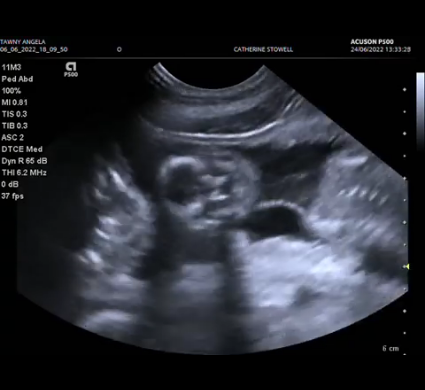

Tawny’s puppies are developing beautifully. The skulls are now very clear, and they are becoming even more active!